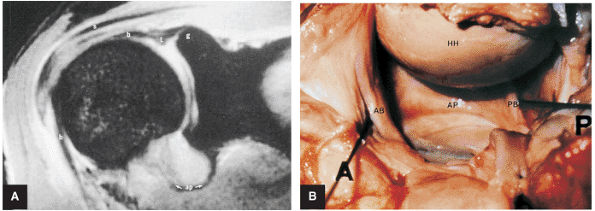

FIGURE 8.73 ● (A) The biceps origin can be located on a T2*-weighted coronal image. The glenoid origin of the long head of the biceps (b) is shown, as are the attachments to the anterior labrum (l) and superior glenoid (g). The biceps courses laterally and exits the joint between the supraspinatus (s) and subscapularis tendons. The axillary pouch (ap) of the IGHL is indicated. The tendon of the long head of the biceps enters the intertubercular groove under the transverse ligament. (B) Gross dissection demonstrates the anterior band (AB) and posterior band (PB) of the IGHL complex. This surgical view is from the perspective of viewing inferiorly into the axillary pouch. The anterior (A), posterior (P), and humeral head (HH) are indicated. Both the biceps tendon and posterior band contribute to the posterior labrum.

|